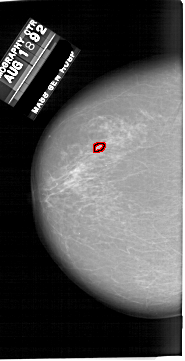

A_1649_1.LEFT_CC

LEFT_CC LINES 6481 PIXELS_PER_LINE 3316 BITS_PER_PIXEL 12 RESOLUTION 43.5 OVERLAY

FILE: A_1649_1.LEFT_CC.OVERLAY

TOTAL_ABNORMALITIES 1

ABNORMALITY 1

LESION_TYPE CALCIFICATION TYPE PLEOMORPHIC DISTRIBUTION CLUSTERED

ASSESSMENT 4

SUBTLETY 4

PATHOLOGY BENIGN

TOTAL_OUTLINES 1